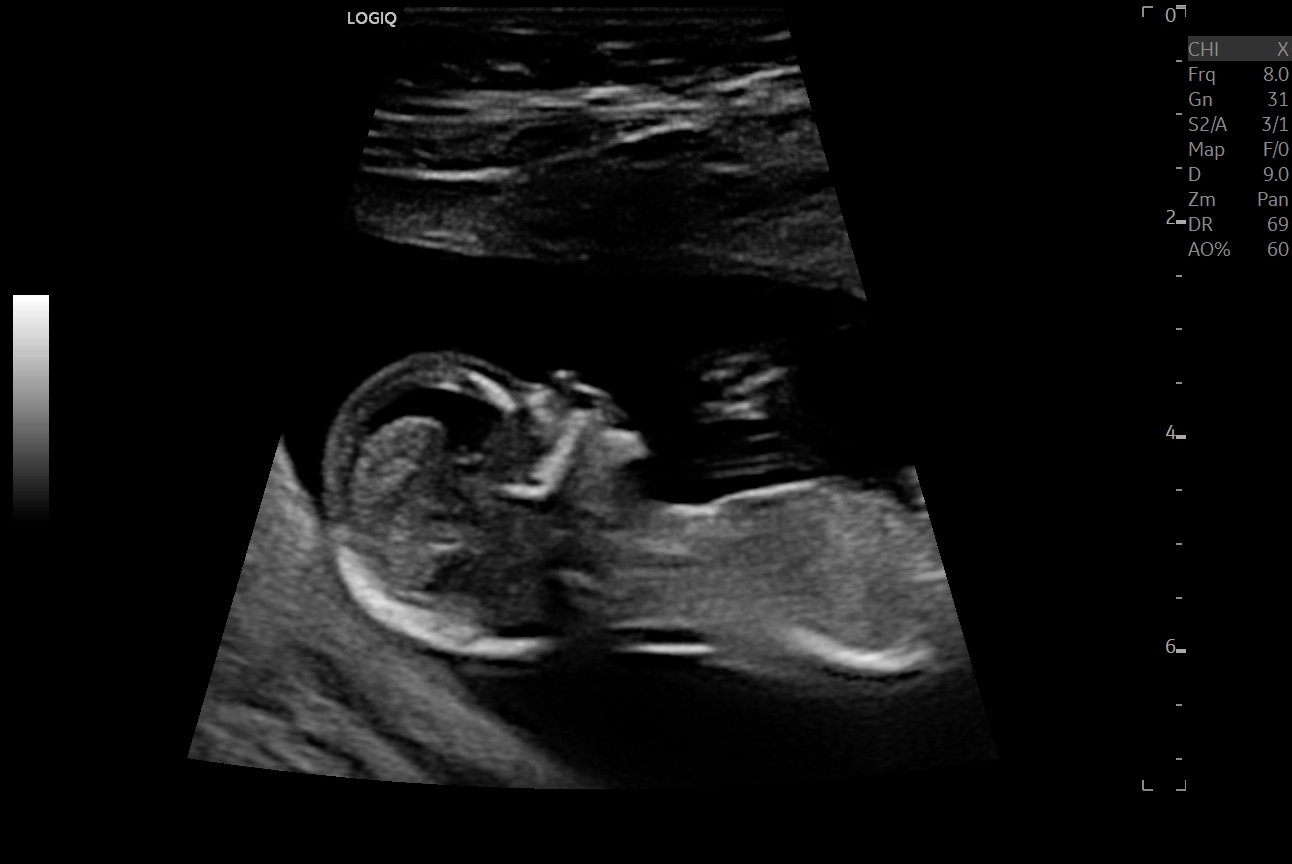

Just got home from our 13 week scan. Would love your thoughts on whether baby is pink or blue! The nub looks girly to me but then later on in the scan the sonographer went down around in a type of potty shot and I thought I saw something between the legs, so now I'm not so sure (didn't get a photo when she went in for the potty shot, she said it was too early to tell)... are potty shots reliable for gender at 13 weeks? If I hadn't seen that potty shot I'd have guessed girly?

I read the nub thread before we went and didn’t take my eyes off the screen as the somographer scanned me, and didn’t see any stacking at all, just those lines (I remember clearly seeing stacking and a little triangle with DS2 at his 12 week scan). Baby was quite curled up during these shots.

Edit: Just talked to DH about the potty shot and he said that was a shot of the baby's head, lol! I’ve included an earlier shot she did of baby’s femurs (legs) in case that gives any clues.